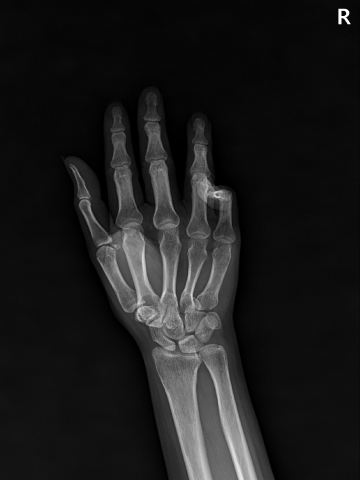

수술전

2022.04.29

수술후

2023.01.04